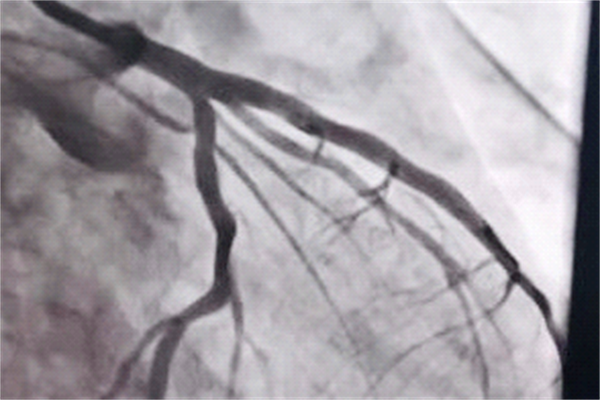

时间就是心肌,时间就是生命。这句话道出争分夺秒的救治对于心肌梗死患者预后的重要性。经过30分钟奋战,成功为患者实施“冠状动脉球囊扩张成形术➕血栓抽吸术”,开通闭塞血管,为患者抢救赢得时间,挽救了患者的生命。心内科团队凭借精准的判断、精湛的技艺和稳定的心理素质,自主圆满完成了犍为县人民医院首例急诊PCI手术。

PCI术后造影